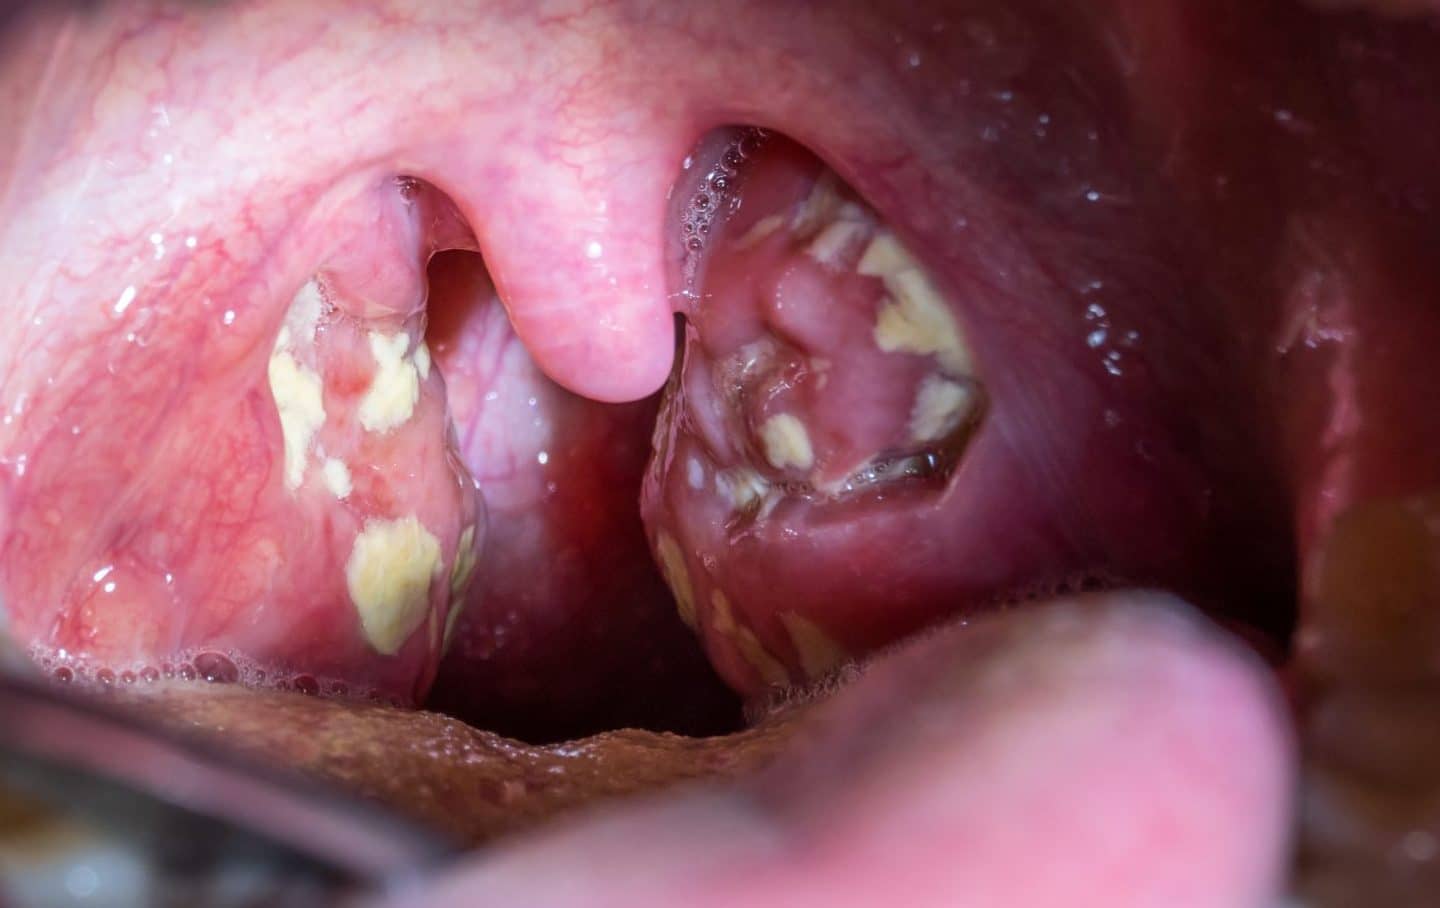

A 19-year-old woman presents to the family medical center with a 2-week history of a sore throat. She says that she has felt increasingly tired during the day and has a difficult time staying awake during her classes at the university. She appears well-nourished with a low energy level. Her vital signs include the following: the heart rate is 82/min, the respiratory rate is 14/min, the temperature is 37.8°C (100.0°F), and the blood pressure is 112/82 mm Hg. Inspection of the pharynx is depicted in the picture. Palpation of the neck reveals posterior cervical lymphadenopathy. The membrane does not bleed upon scraping. What is the most specific finding for detecting the syndrome described in the vignette?

A 17-year-old boy is admitted to the emergency department with a history of fatigue, fever of 40.0°C (104.0°F), sore throat, and enlarged cervical lymph nodes. On physical examination, his spleen and liver are not palpable. A complete blood count is remarkable for atypical reactive T cells. An examination of his tonsils is shown in the image below. Which of the following statements is true about the condition of this patient?